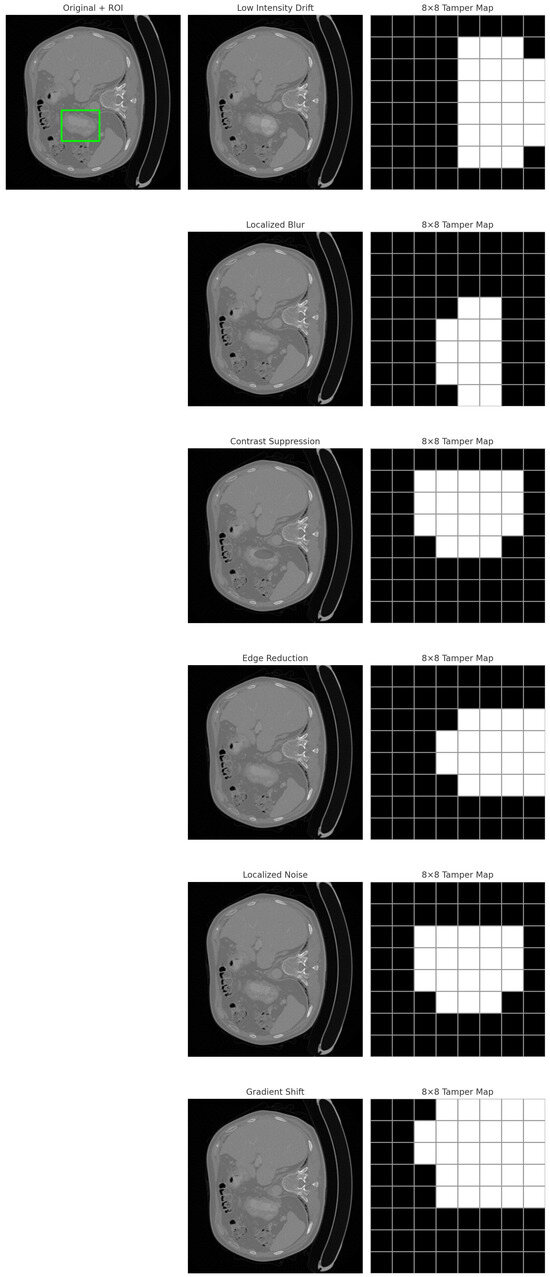

A Non-Embedding Watermarking Framework Using MSB-Driven Reference Mapping for Distortion-Free Medical Image Authentication

Ensuring the integrity of medical images is essential to securing clinical workflows, telemedicine platforms, and healthcare IoT environments. Existing watermarking and reversible data-hiding approaches often modify pixel intensities, reducing diagnostic fidelity, introducing embedding constraints, or causing instability under compression and format conversion. This [...] Read more.

Ensuring the integrity of medical images is essential to securing clinical workflows, telemedicine platforms, and healthcare IoT environments. Existing watermarking and reversible data-hiding approaches often modify pixel intensities, reducing diagnostic fidelity, introducing embedding constraints, or causing instability under compression and format conversion. This work proposes a distortion-free, non-embedding authentication framework that leverages the inherent stability of the most significant bit (MSB) patterns in the Non-Region of Interest (NROI) to construct a secure and tamper-sensitive reference for the diagnostic Region of Interest (ROI). The ROI is partitioned into fixed blocks, each producing a 256-bit SHA-256 signature. Instead of embedding this signature, each hash bit is mapped to an NROI pixel whose MSB matches the corresponding bit value, and only the encrypted coordinates of these pixels are stored externally in a secure database. During verification, hashes are recomputed and compared bit-by-bit with the MSB sequence extracted from the referenced NROI coordinates, enabling precise block-level tamper localization without modifying the image. Extensive experiments conducted on MRI (OASIS), X-ray (ChestX-ray14), and CT (CT-ORG) datasets demonstrate the following: (i) perfect zero-distortion fidelity; (ii) stable and deterministic MSB-class mapping with abundant coordinate diversity; (iii) 100% detection of intentional ROI tampering with no false positives across the six clinically relevant manipulation types; and (iv) robustness to common benign Non-ROI operations. The results show that the proposed scheme offers a practical, secure, and computationally lightweight solution for medical image integrity verification in PACS systems, cloud-based archives, and healthcare IoT applications, while avoiding the limitations of embedding-based methods. Full article